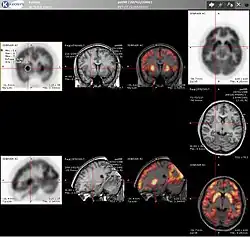

Combination of PET with CT or MRI

PET scans are increasingly read alongside CT or MRI scans, with the combination (co-registration) giving both anatomic and metabolic information (i.e., what the structure is, and what it is doing biochemically). Because PET imaging is most useful in combination with anatomical imaging, such as CT, modern PET scanners are now available with integrated high-end multi-detector-row CT scanners (PET–CT). Because the two scans can be performed in immediate sequence during the same session, with the patient not changing position between the two types of scans, the two sets of images are more precisely registered, so that areas of abnormality on the PET imaging can be more perfectly correlated with anatomy on the CT images. This is very useful in showing detailed views of moving organs or structures with higher anatomical variation, which is more common outside the brain.

For brain imaging, registration of CT, MRI and PET scans may be accomplished without the need for an integrated PET–CT or PET–MRI scanner by using a device known as the N-localizer.[31][74][75][76]